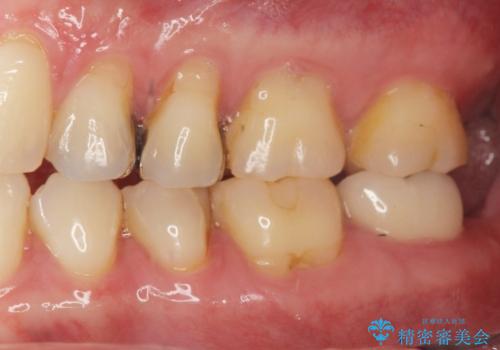

- ジルコニアクラウン・仮歯 12.1万円×2費用は治療当時の料金となります

白い被せ物を入れたことにより銀が目立たなくなり

染みることもなくなりました。

ご希望に沿った治療となり大変満足して頂けました。